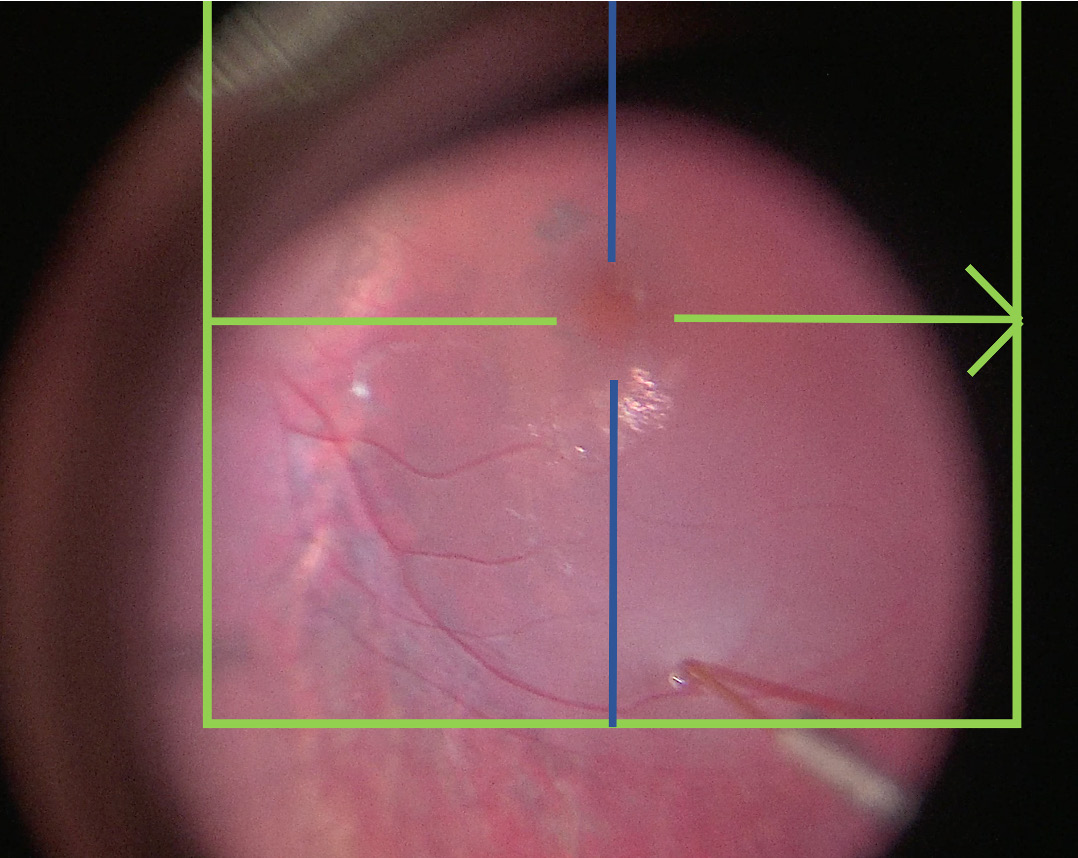

視網(wǎng)膜下注射基因療法的外科技術(shù)在技術(shù)上要求很高,具有挑戰(zhàn)性,因?yàn)樵诒O(jiān)測(cè)泡狀出血形成和傳播的液體分布時(shí),識(shí)別套管深度和穿透是困難的。16-18外科醫(yī)生的手必須穩(wěn)定,并且在大約兩到五分鐘內(nèi)只進(jìn)行小的調(diào)整,同時(shí)變化注射壓力并使用腳踏板調(diào)整顯微鏡控制。可能的并發(fā)癥包括治療不足或不成功,載體從泡狀出血中逸出,或外科創(chuàng)傷。治療不足可能發(fā)生在未能傳遞全部載體量,未能覆蓋所需的治療區(qū)域,或?qū)⑤d體傳遞到錯(cuò)誤的眼內(nèi)層(例如脈絡(luò)膜上而不是視網(wǎng)膜下)。當(dāng)擴(kuò)大視網(wǎng)膜切口,無(wú)意中在嘗試接合主要視網(wǎng)膜切開(kāi)口時(shí)創(chuàng)建第二個(gè)視網(wǎng)膜切口,或在創(chuàng)建多個(gè)泡狀出血時(shí)泡狀出血合并時(shí),會(huì)發(fā)生載體回流。當(dāng)高注射壓力對(duì)RPE或黃斑施加過(guò)大壓力,導(dǎo)致yongjiu性RPE變形或全層黃斑孔時(shí),會(huì)產(chǎn)生外科創(chuàng)傷。術(shù)中光學(xué)相干斷層掃描(術(shù)中OCT)提供了實(shí)時(shí)信息向外科醫(yī)生反饋,關(guān)于穿刺進(jìn)入后段結(jié)構(gòu)的深度,注射液體的分布和傳播,載體回流,以及在這些操作過(guò)程中黃斑的完整性。這提高了視網(wǎng)膜基因增強(qiáng)療法程序的安全性和治療傳遞的準(zhǔn)確性。